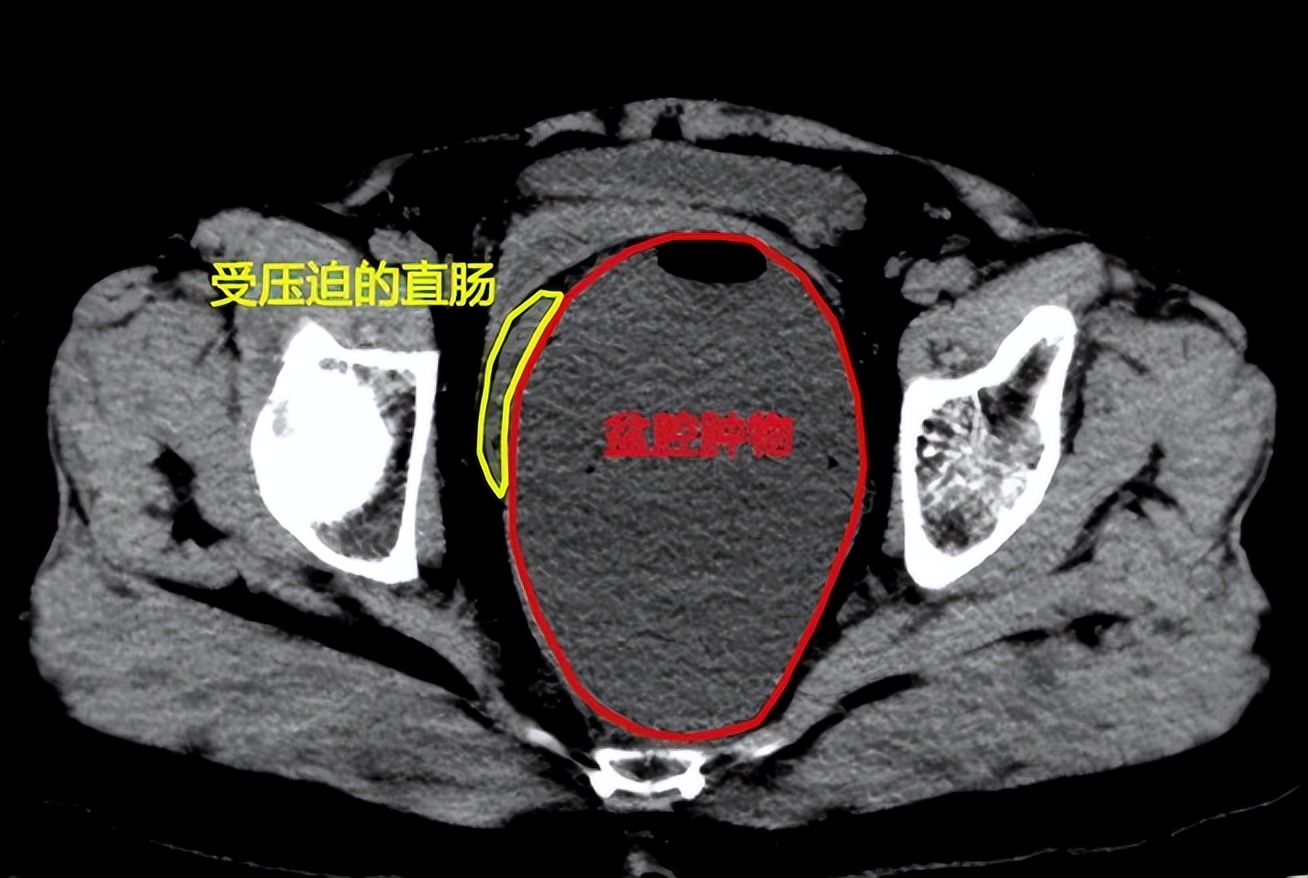

图片说明:腹部CT显示张女士盆腔内巨大囊性肿物压迫直肠产生移位,盆腔核磁共振成像显示盆腔肿物与骶前血管关系密切

“患者肿物巨大,最大直径达18cm,子宫,膀胱及直肠均受压,且肿物考虑为后腹膜来源,不排除囊性畸胎瘤,手术难度很大”。妇科会诊专家对患者进行了妇科内诊检查,建议手术治疗,并提出如肿瘤为腹膜后来源,存在无法完全切除可能。